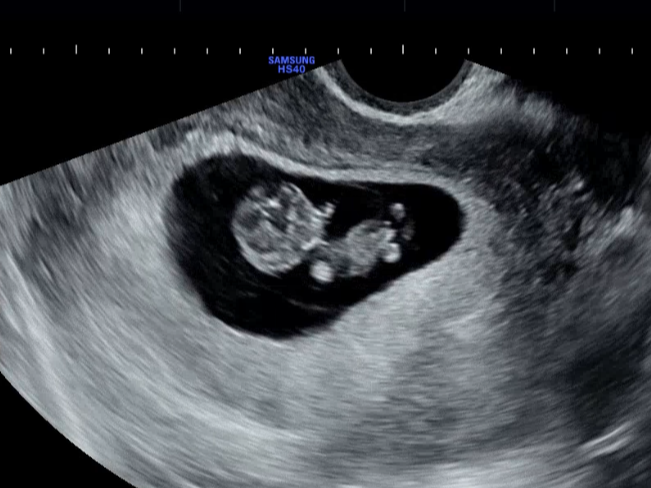

태아 초음파 리즈라는 8, 9주 차 초음파..🫶🏻

뽀용뽀용 움직이는 모습이 너무 귀여워요ㅠㅠ

이제는 태아에게 손가락, 발가락이 생기고

손을 움직이기도 하는 시기예요.

이목구비도 점점 뚜렷해지고,

생식기도 발달해 성별이 슬슬 구분될 시기이죠.

이제 초음파로 보면 '사람 같아졌다~' 싶어요.

태아의 크기와 형태 : 딸기만 해요!

12주쯤 되면 태아는 약 5~6cm,

무게는 14g 정도까지 자라서

딸기 한 알만 해져요!

이전엔 태아가 너무 작아서 질 초음파로 확인했다면

이제는 복부 초음파에서도 아기를 볼 수 있어요.